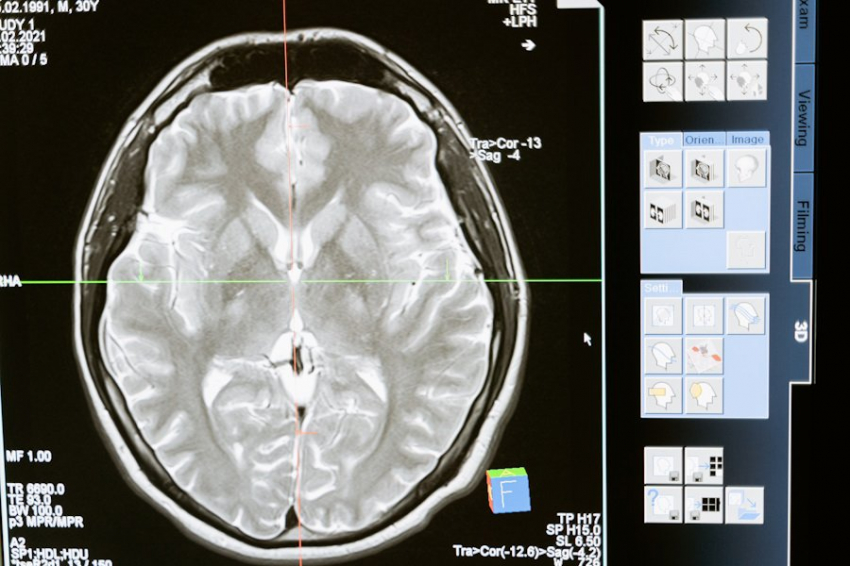

В новом исследовании профессор Кей Нагашима из Лаборатории температуры тела и жидкости Факультета гуманитарных наук Университета Васэда, Япония, и Хиронори Ватанабэ из Университета Васэда в сотрудничестве с другими учеными использовали электроэнцефалографию (ЭЭГ) для картирования реакции мозга на высокие и низкие температуры и выяснения закономерностей активности.

В этом исследовании 20 участников подвергались различным температурным воздействиям на правый указательный и средний пальцы. Температурные воздействия проводились импульсами в течение 15 секунд с 10-секундным прерывистым повышением температуры до 32 ˚C. Нейронная активность мозга в ответ на две разные температуры, 40 ˚C и 24 ˚C, регистрировалась с помощью носимого устройства ЭЭГ. Исследование было опубликовано в журнале Neuroscience.

Записи были проанализированы, чтобы выявить закономерности активности мозга, специфичные для региона и времени. Кластерная активность мозга была обнаружена в десяти различных областях коры. Интересно, что как высокие, так и низкие температуры вызывали активность мозга в одних и тех же десяти областях. Однако ЭЭГ различалась в ответ на два типа температурных ощущений. «Различия в этих закономерностях активности позволят различать разницу температур, что приведет к разному поведению», — говорит Нагашима.